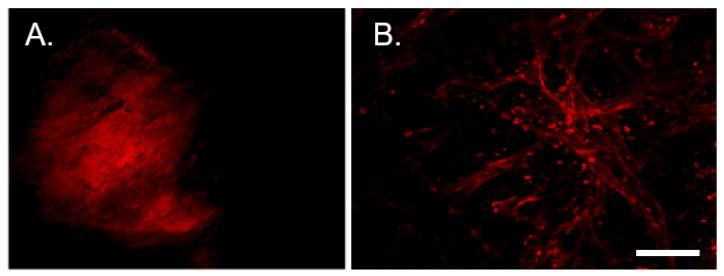

Dense tumor innervation is associated with enhanced cancer progression and poor prognosis. We observed innervation in breast, prostate, pancreatic, lung, liver, ovarian, and colon cancers. Defining innervation in high-grade serous ovarian carcinoma (HGSOC) was a focus since sensory innervation was observed whereas the normal tissue contains predominantly sympathetic input. The origin, specific nerve type, and the mechanisms promoting innervation and driving nerve-cancer cell communications in ovarian cancer remain largely unknown. The technique of neuro-tracing enhances the study of tumor innervation by offering a means for identification and mapping of nerve sources that may directly and indirectly affect the tumor microenvironment. Here, we establish a murine model of HGSOC and utilize image-guided microinjections of retrograde neuro-tracer to label tumor-infiltrating peripheral neurons, mapping their source and circuitry. We show that regional sensory neurons innervate HGSOC tumors. Interestingly, the axons within the tumor trace back to local dorsal root ganglia as well as jugular-nodose ganglia. Further manipulations of these tumor projecting neurons may define the neuronal contributions in tumor growth, invasion, metastasis, and responses to therapeutics.

密集的肿瘤神经支配与癌症的进展和预后不良有关。我们观察到乳腺癌、前列腺癌、胰腺癌、肺癌、肝癌、卵巢癌和结肠癌存在神经支配。由于观察到感觉神经支配,而正常组织主要含有交感神经输入,因此高等级浆液性卵巢癌(HGSOC)中的神经支配的定义是一个重点。神经支配的起源、特定神经类型以及促进神经-癌细胞通讯的机制在卵巢癌中仍然很大程度上未知。神经追踪技术通过提供一种识别和绘制可能直接和间接影响肿瘤微环境的神经来源的方法,增强了对肿瘤神经支配的研究。在这里,我们建立了 HGSOC 的小鼠模型,并利用图像引导的逆行神经示踪剂微注射来标记肿瘤浸润的周围神经元,绘制其来源和回路。我们表明,局部感觉神经元支配 HGSOC 肿瘤。有趣的是,肿瘤内的轴突回溯到局部背根神经节和颈静脉神经节。对这些肿瘤投射神经元的进一步操作可能会确定神经元在肿瘤生长、侵袭、转移和对治疗的反应中的贡献。